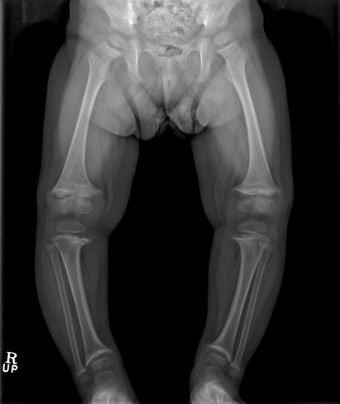

또한 오목가슴이나 척추의 변형(후만, 전만, 측만 등)을 초래하기도 합니다. 팔다리는 손목, 발목 부위 뼈 부분이 두꺼워지면서 두드러지게 만져지고, 약해진 다리로 몸무게를 지탱할 수 없어 다리가 휘어지며(안짱다리 또는 밭장다리), 구루병으로 성장 자체에 문제가 생기기도 합니다.

구루병은 특이한 임상 증상과 뼈의 엑스선 검사, 생화학적 검사를 종합해 진단합니다.